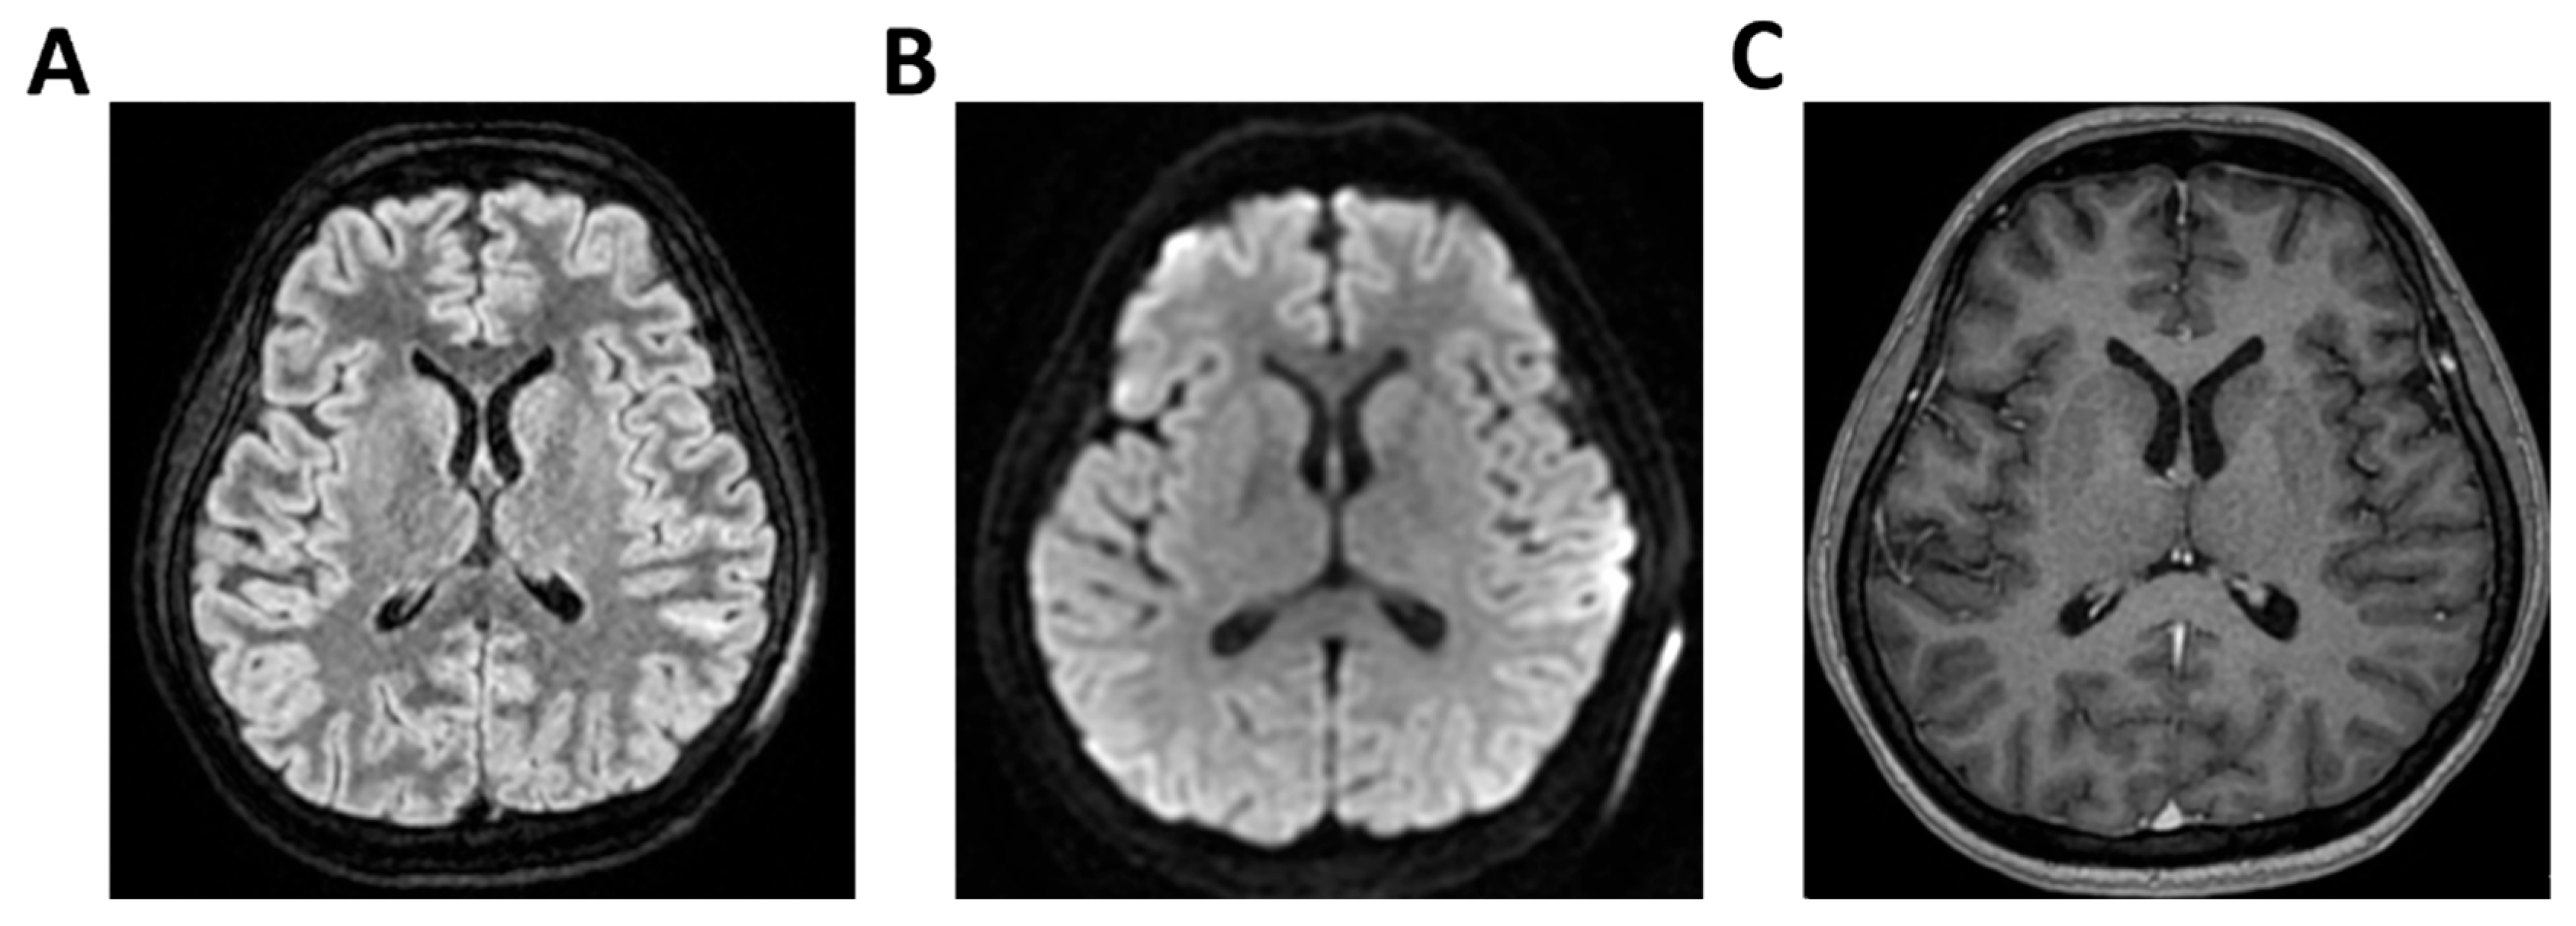

Figure 6.

MRI of patient 1 group 2. A 63-year-old man with a history of hypertension, dyslipidemia, and prior pulmonary lobectomy was admitted to the ER in a drowsy but verbally responsive state. His wife reported a recent episode of vomiting followed by loss of consciousness and tonic–clonic seizures. He was uncooperative and tremulous but afebrile, although a febrile episode had occurred in the preceding days. A lumbar puncture led to a diagnosis of Neisseria meningitidis type B meningitis. Ceftriaxone 2 g IV every 12 h was initiated. Brain CT, chest CT, and angio-CT of the epiaortic vessels showed no acute abnormalities. Due to clinical deterioration and a further seizure with hypotension, the patient was sedated, intubated, and experienced an episode of ventricular tachycardia during CT imaging, requiring IV Amiodarone. The patient was transferred to the ICU. On day 2, TCCD showed no significant flow abnormalities, with only mild asymmetry in PI (1.11 right, 1.4 left), without evidence of intracranial hypertension. (A) MRI exam with perfusion study reveal areas of altered signal intensity, hyperintense on 3D axial FLAIR sequence, (B) with diffusion restriction in axial DWI sequence, indicative of subacute inflammatory processes. These areas were scattered, the most significant is located along the subpial cortical surfaces of the left precentral and supramarginal gyri. Additionally, MRI exam demonstrates leveled material of likely inflammatory nature in both occipital horns of the lateral ventricles (A,B). (C) MRI perfusion with ASL sequence shows normal and symmetrical CBF values. Blue circles indicate the region of interest (ROI) used for quantitative CBF analysis.

Figure 7.

MRI of patient 2 group 2. A 45-year-old male without prior clinical conditions experienced chills and general discomfort and dizziness. He arrived at the ER unresponsive with a GCS score of 10. A brain CT scan showed no signs of hemorrhage or thrombosis, and a lumbar puncture was carried out for microbiological and biochemical analysis. Empirical therapy with Rocephin, Zovirax, and Ampicillin was initiated, and both neurology and intensive care consultations were obtained. Given the likely progressive clinical condition, the patient was sedated, intubated, and transferred to the ICU for further treatment. On the second day, the patient underwent a TCCD, which documented a PI of 1.32 on the right and 1.28 on the left (A) 3D axial FLAIR, (B) axial DWI and (C) 3D axial T1 FSPGR after administration of contrast medium demonstrate normal morphology and signal intensity of brain tissue. No evidence of acute or chronic infarction, demyelination or mass lesion. Supratentorial and infratentorial ventricular system is normal in size and configuration, with no midline shift or hydrocephalus. No signs of intracranial hypertension. Sulci and subarachnoid spaces are within normal limits for age. (D) MRI perfusion with ASL sequence shows normal and symmetrical CBF values. Blue circles indicate the ROI used for quantitative CBF analysis.

Figure 8.

MRI of patient 3 group 2. A 67-year-old woman with hypertension, depressive disorder, and hypothyroidism was brought to the ER in a confused state, following three days of abdominal pain, fever, neck pain, and headache. On arrival, she was drowsy but responsive to verbal stimuli and able to follow simple commands. Total-body CT showed no cranial or abdominal pathology except for a 6 cm rectal fecaloma; lungs were clear. A lumbar puncture revealed cloudy CSF with 1100 cells/mm3. FilmArray was positive for S. pneumoniae. She was treated with Rocephin and Tazocin and transferred to our ICU. On day 2, TCCD showed no flow abnormalities, with PI values of 1.2 (right) and 1.1 (left). (A) 3D axial FLAIR sequence shows multiple hyperintense areas, without significant diffusion restriction in axial DWI sequence, localized in bilateral corona radiata and centrum semiovale and leveled material of likely inflammatory nature in both occipital horns of the lateral ventricles. (B) The perfusion study revealed normal and symmetrical CBF values. Blue and yellow circles indicate the ROI used for quantitative CBF analysis.

3.2. Group 2: TCCD and Perfusion MRI with ASL

In the second group five patients were included. The mean age was 55.4 years (median 63, range 35–67), and three (60%) were male.

Etiological diagnoses were heterogeneous: meningococcal meningitis (n = 1, 20%) (case 1), PML (n = 1, 20%) (case 2), Listeria monocytogenes meningoencephalitis (n = 1, 20%) (case 3), meningoencephalitis of undetermined origin (n = 1, 20%) (case 4), and pneumococcal meningitis (n = 1, 20%) (case 5). Patients underwent MRI with ASL to assess cerebral perfusion. Three patients had normal TCCD findings (PI ≤ 1.4) and symmetrical CBF (differences <15% between hemispheres). ASL imaging confirmed the absence of perfusion deficits, even in cases where FLAIR imaging revealed mild inflammatory changes. All three patients recovered their baseline neurological function at 28 days (Table 3 and Figure 6, Figure 7 and Figure 8).